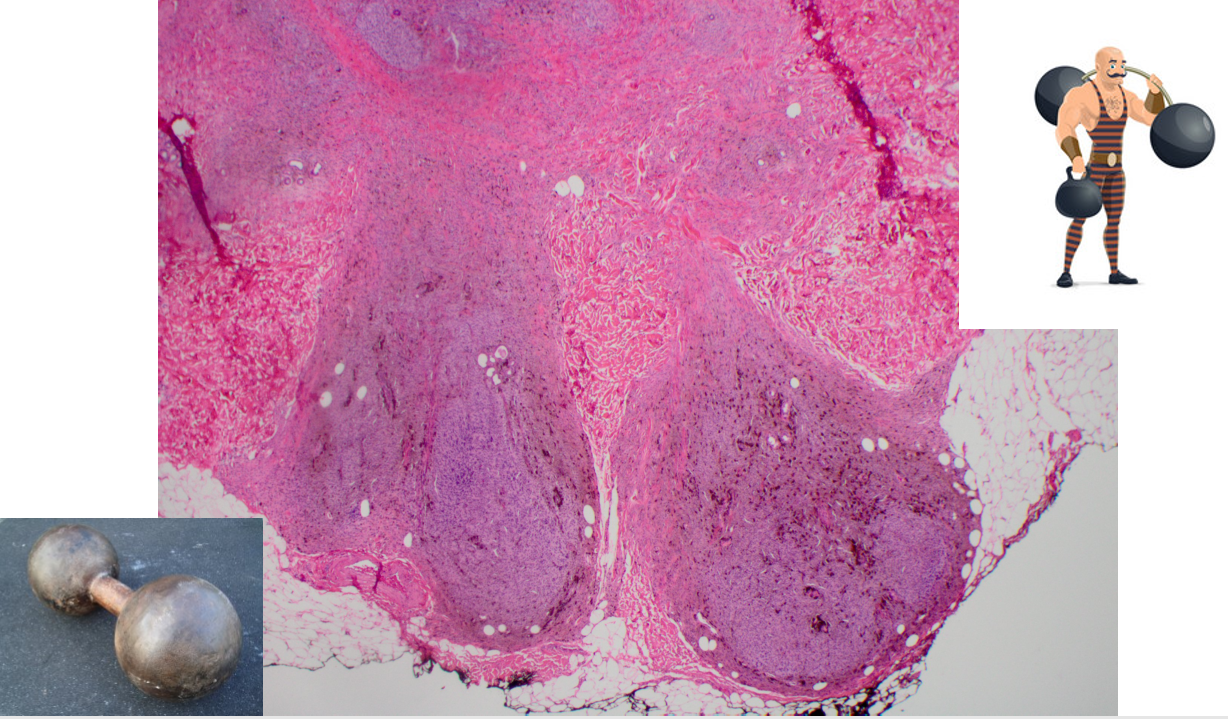

Ossifying fibromyxoid tumor of soft parts

*shell of bone present

*fibromyxoid matrix